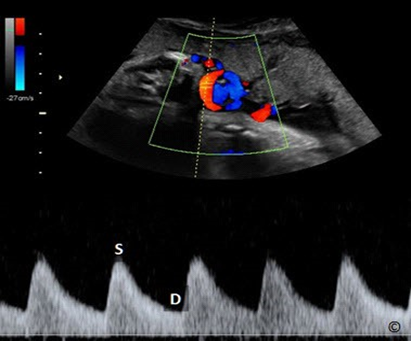

Quản lý thai kỳ sẽ phụ thuộc vào mức độ nặng của tình trạng thai giới hạn tăng trưởng trong tử cung. Quan trọng nhất là quyết định thời điểm nào sẽ chấm dứt thai kỳ (có thể sinh thường hoặc mổ lấy thai theo chỉ định sản khoa). Bác sĩ đánh giá điều này dựa vào tuổi thai, siêu âm sinh trắc thai, lượng ối, siêu âm màu (Doppler mạch máu), các yếu tố nguy cơ khác cũng như mong muốn của gia đình.